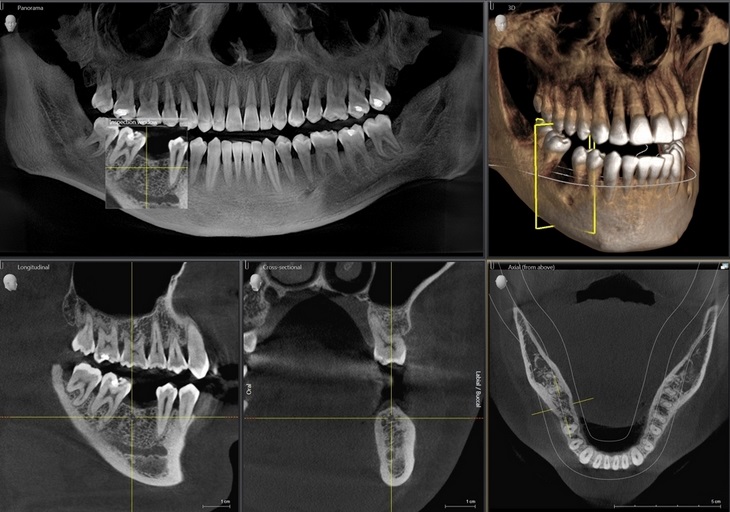

- Компьютерная томография (КТ)⁚ Обеспечивает трехмерное изображение челюстей, позволяя более точно оценить степень разрушения костной ткани и расположение патологических очагов. КТ особенно полезна при планировании сложных хирургических вмешательств.

- Панорамная рентгенография (ортопантомограмма)⁚ Позволяет получить обзорное изображение всей челюсти, что полезно для выявления множественных очагов поражения.

Интерпретация рентгенограмм требует опыта и знаний. Врач-стоматолог анализирует ширину периодонтальной щели, наличие деструкции костной ткани, форму и размеры патологических очагов. Эти данные, в сочетании с клинической картиной, позволяют поставить точный диагноз и определить тактику лечения.